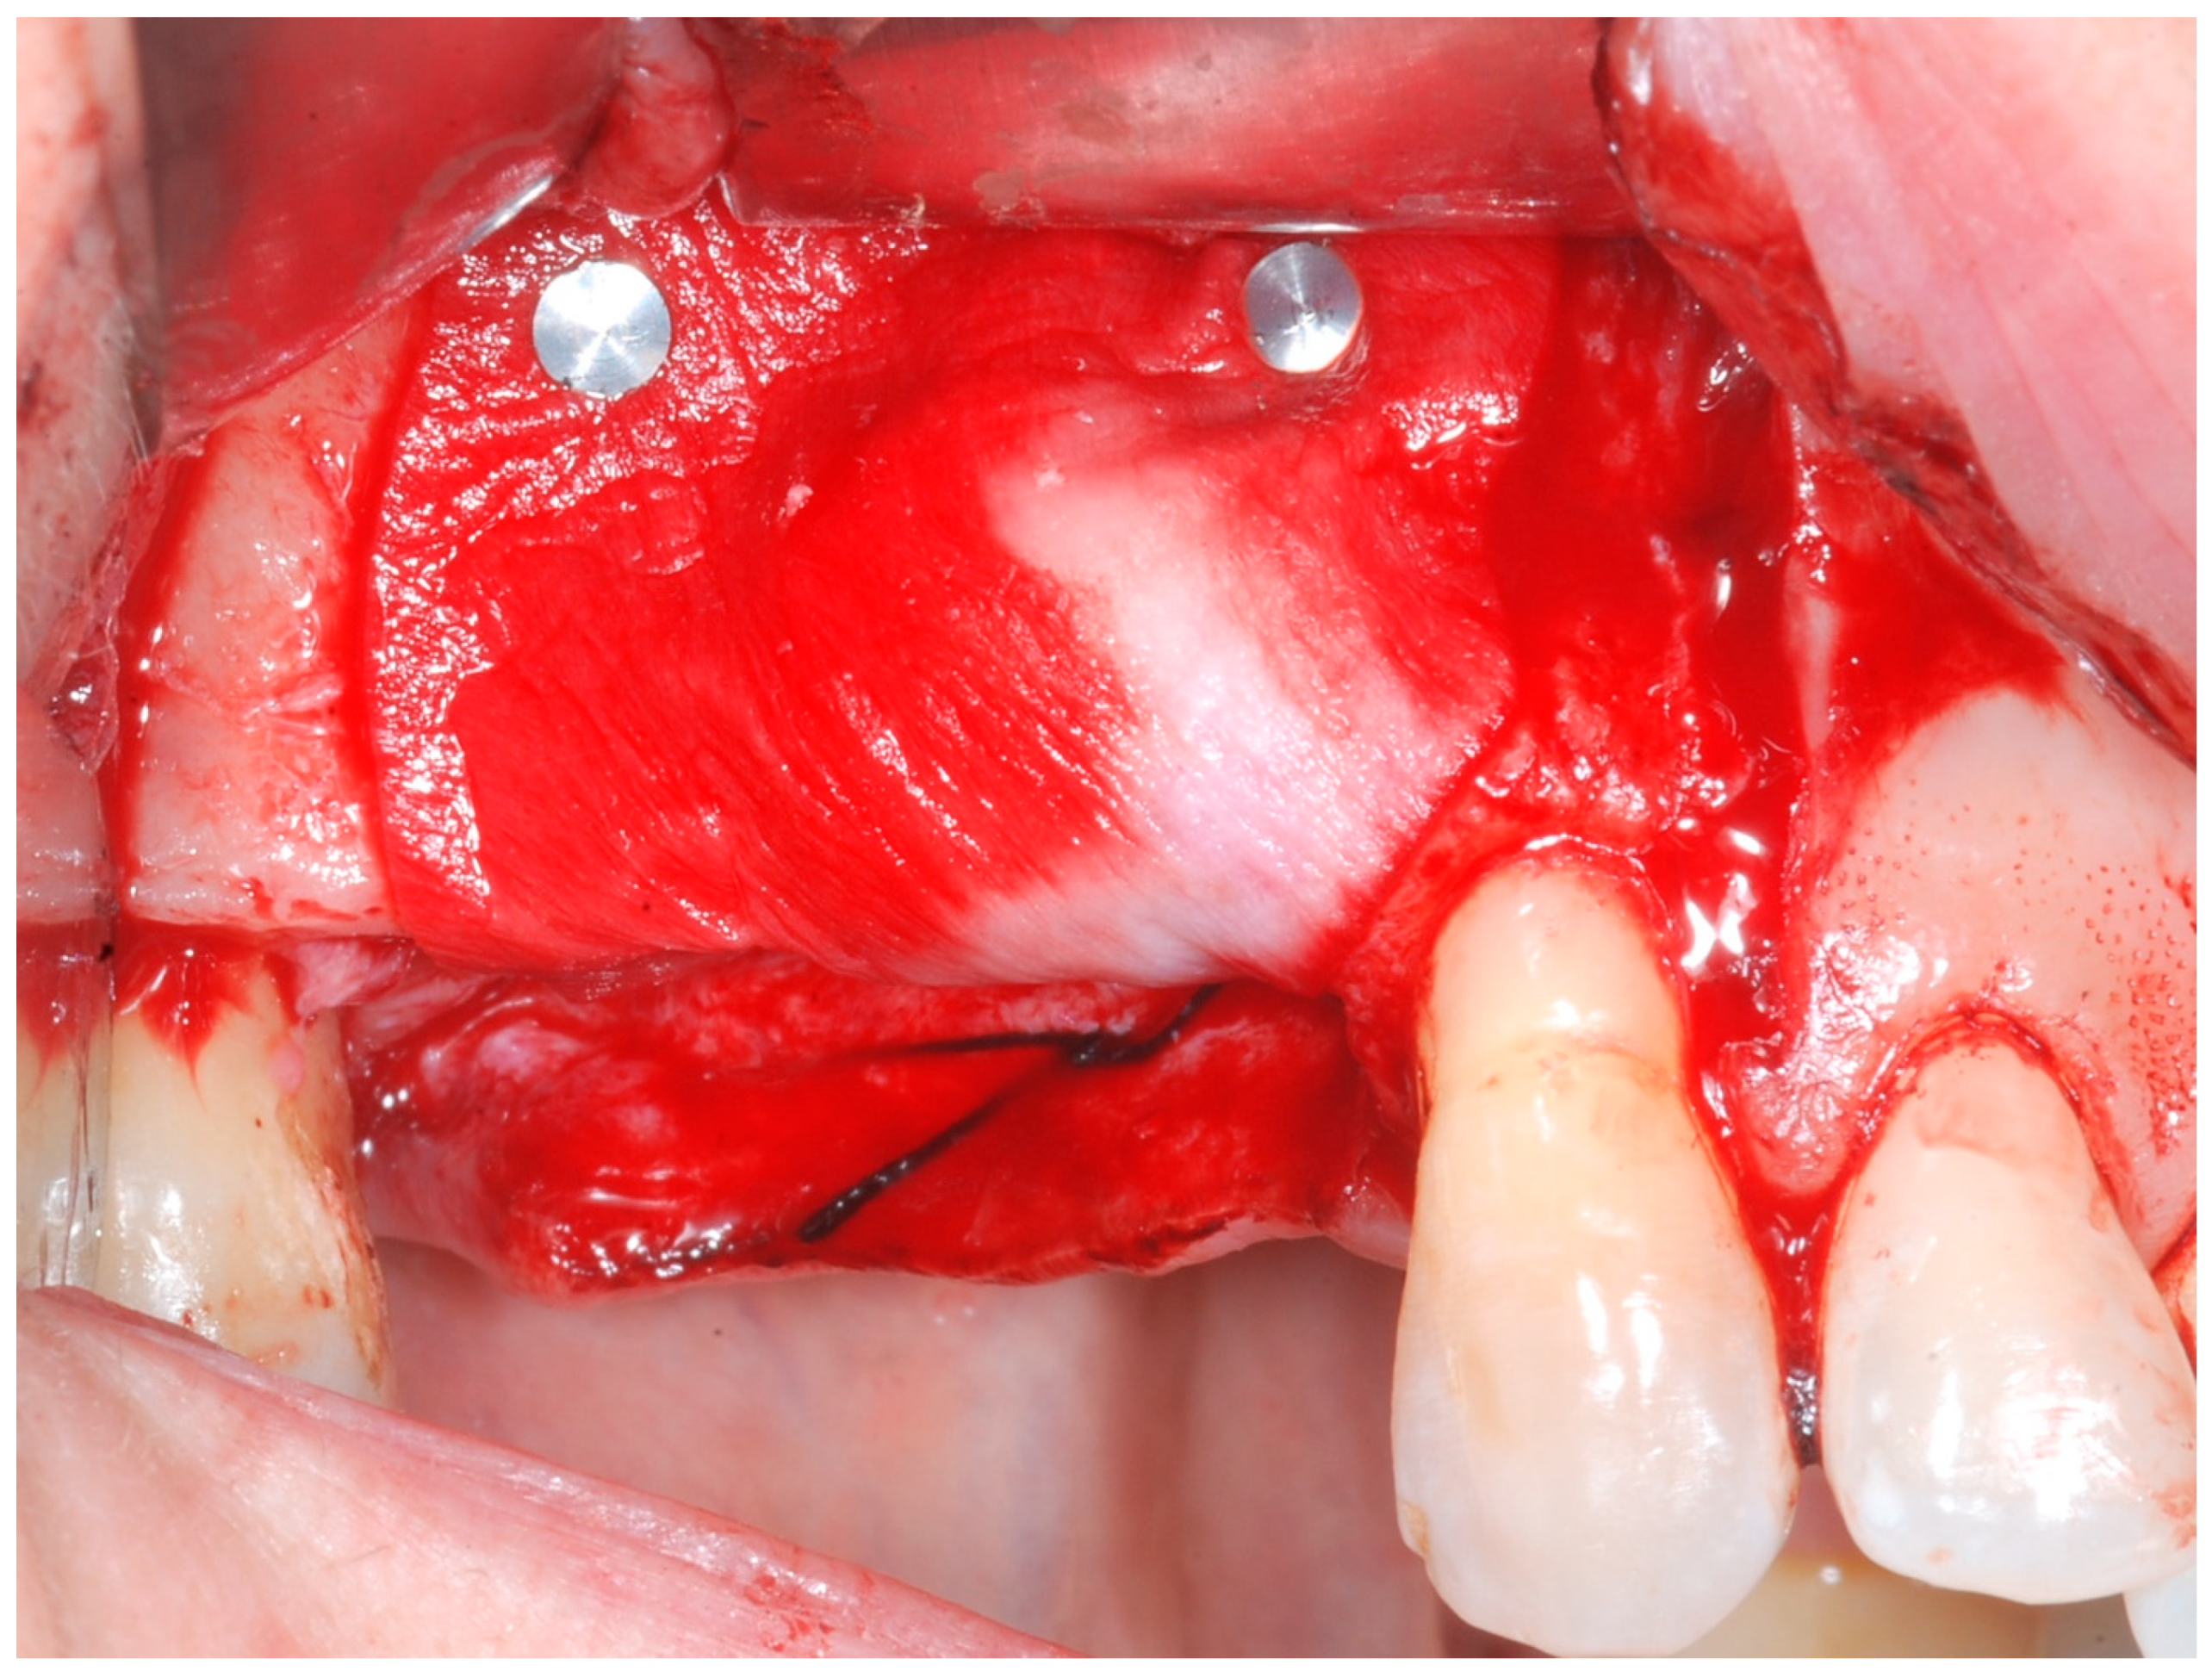

2.4. Re-Entry Surgery (T1)

Six months following augmentation, re-entry surgery was carried out to uncover the implants and connect the healing abutments. Following chlorhexidine rinses and the injection of local anesthetics, crestal incisions as well as releasing incisions along the same lines as the ones during augmentation surgery were performed. Mucoperiosteal flaps were raised in order to visualize the augmented bone volume (Figure 9 and Figure 10).

During the 6-month period from T0 to T1, healing proceeded uneventfully in all patients, with no major complications or biocompatibility issues. No allergic reactions were observed. No complications such as flap dehiscence, membrane exposure, wound infection, fistulae with pus discharge, or foreign body reactions were noticed. None of the surgical sites had to be re-opened earlier. During the re-entry phase, in each surgical site no membrane remnants could be detected. Augmented newly formed hard tissue was observed clinically, with macroscopic features of healthy, bleeding, newly formed bone. Remnants of DBBM granules were occasionally visible and appeared firmly attached to the regenerated hard tissue, with no macroscopic signs of fibrous encapsulation. A thin layer of pseudo-periosteum with a thickness < 1 mm was seldomly observed. In all cases, implants appeared clinically stable, with no residual bony dehiscences or fenestrations at the buccal aspect.

Figure 9. Reopening surgery showing no membrane residues and obtained buccal bone thickness.

Medicina 61 01814 g009

Figure 10. Reopening surgery showing no membrane residues and obtained buccal bone thickness.